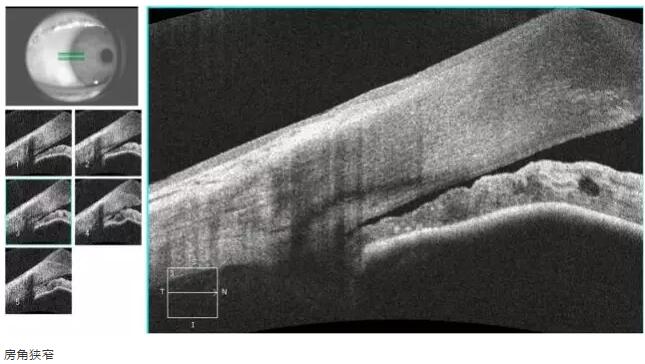

青光眼篇

1:OCT 前节断层扫描可识别出巩膜突、Schwalbe 线 、Schlemm 管 等结构,且辨识度很高,巩膜突(78.9%)、Schwalbe线(93.3%),若对图像进行放大查看, 更佳。

易游体育课堂:后节频域OCT前节模块的运用12.jpg

易游体育课堂:后节频域OCT前节模块的运用13.jpg